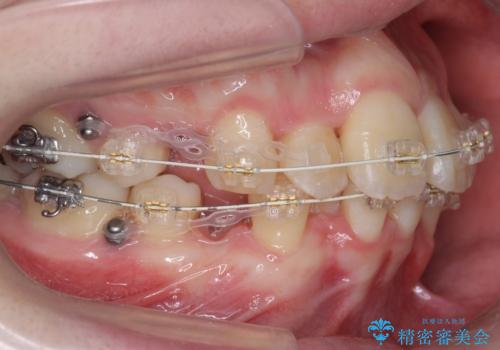

- ワイヤー矯正

- 前歯のがたつき、前突を主訴に来院。

通常前から4番目の歯を抜歯するのですが、左上5番の形が矮小であったため、そちらを抜歯しました。(患者様の希望にそっています。)

前から5番目の歯を抜くと、長くて1年ほど矯正期間が延長しますが、形に異常がない左上4番を抜かずに保存しています。